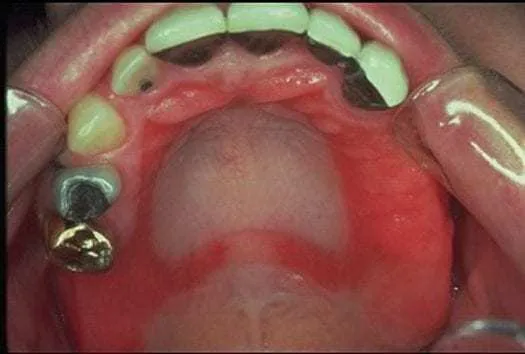

Zmiany na dziąsłach i błonie śluzowej: Zaczerwienienie, obrzęk i zapalenie

Alergia na nikiel może manifestować się również poprzez widoczne zmiany w obrębie jamy ustnej. Często obserwuje się zapalenie błony śluzowej jamy ustnej (stomatitis), które objawia się jako zaczerwienienie, pieczenie i nadwrażliwość. Dziąsła mogą stać się obrzęknięte i zaczerwienione, co jest oznaką zapalenia dziąseł (gingivitis). Te symptomy wskazują na miejscową reakcję alergiczną wywołaną kontaktem z niklem.